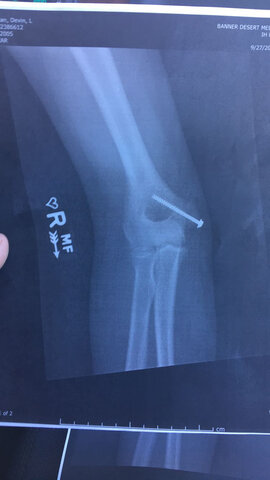

• 8. Broken Elbow

8. Broken Elbow

During the summer going into my 8th grade year I broke my elbow. I was very mad because at the time I played Softball and I couldn't play for a while because it was my throwing arm. I got a screw placed in my elbow to keep it stable and to this day, I still have it in my arm.